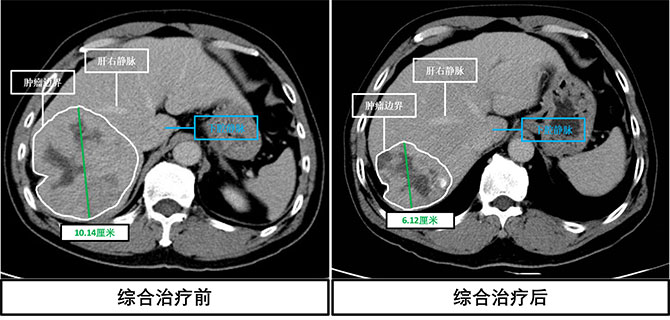

时间到了6个月后,林大叔心脏功能较之前明显改善,虽然心脏射血分数变化不大,但是左心室收缩末直径从明显扩大的60mm缩小到基本正常的44mm(图 1)。肝胆外科特色的肝癌新辅助治疗也非常有成效,林大叔肝脏的肿瘤不仅较前缩小近40%,并且与肝脏重要血管有了一定的安全距离(图 2)。但是这时林大叔对使用的一些药物也出现了一定的副作用和耐药。经过省医肝脏肿瘤多学科诊疗团队(MDT)再次讨论,认为经过肝胆外科及心内科专家双管齐下的治疗下,现在可以在保证患者心功能平稳的情况下,进行微创手术切除肿瘤。

图2 肝脏肿瘤治疗前后对比